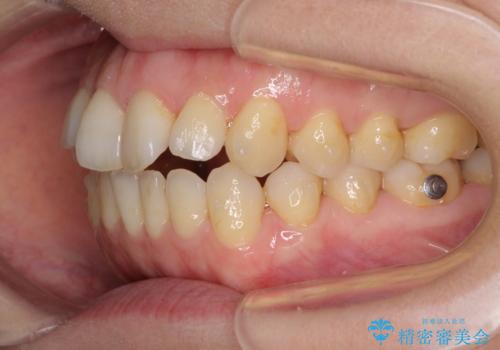

前歯の叢生とオープンバイト インビザラインでの矯正治療

- 前歯の開咬を気にして来院された患者様です。

開咬の治療は、前歯を閉じるように動かすとともに、上下臼歯を圧下(骨内にめり込ませる)させることで進めて行きます。

インビザラインは臼歯の圧下を効果的に行えるため、インビザラインを用いて矯正治療を行うこととしました。